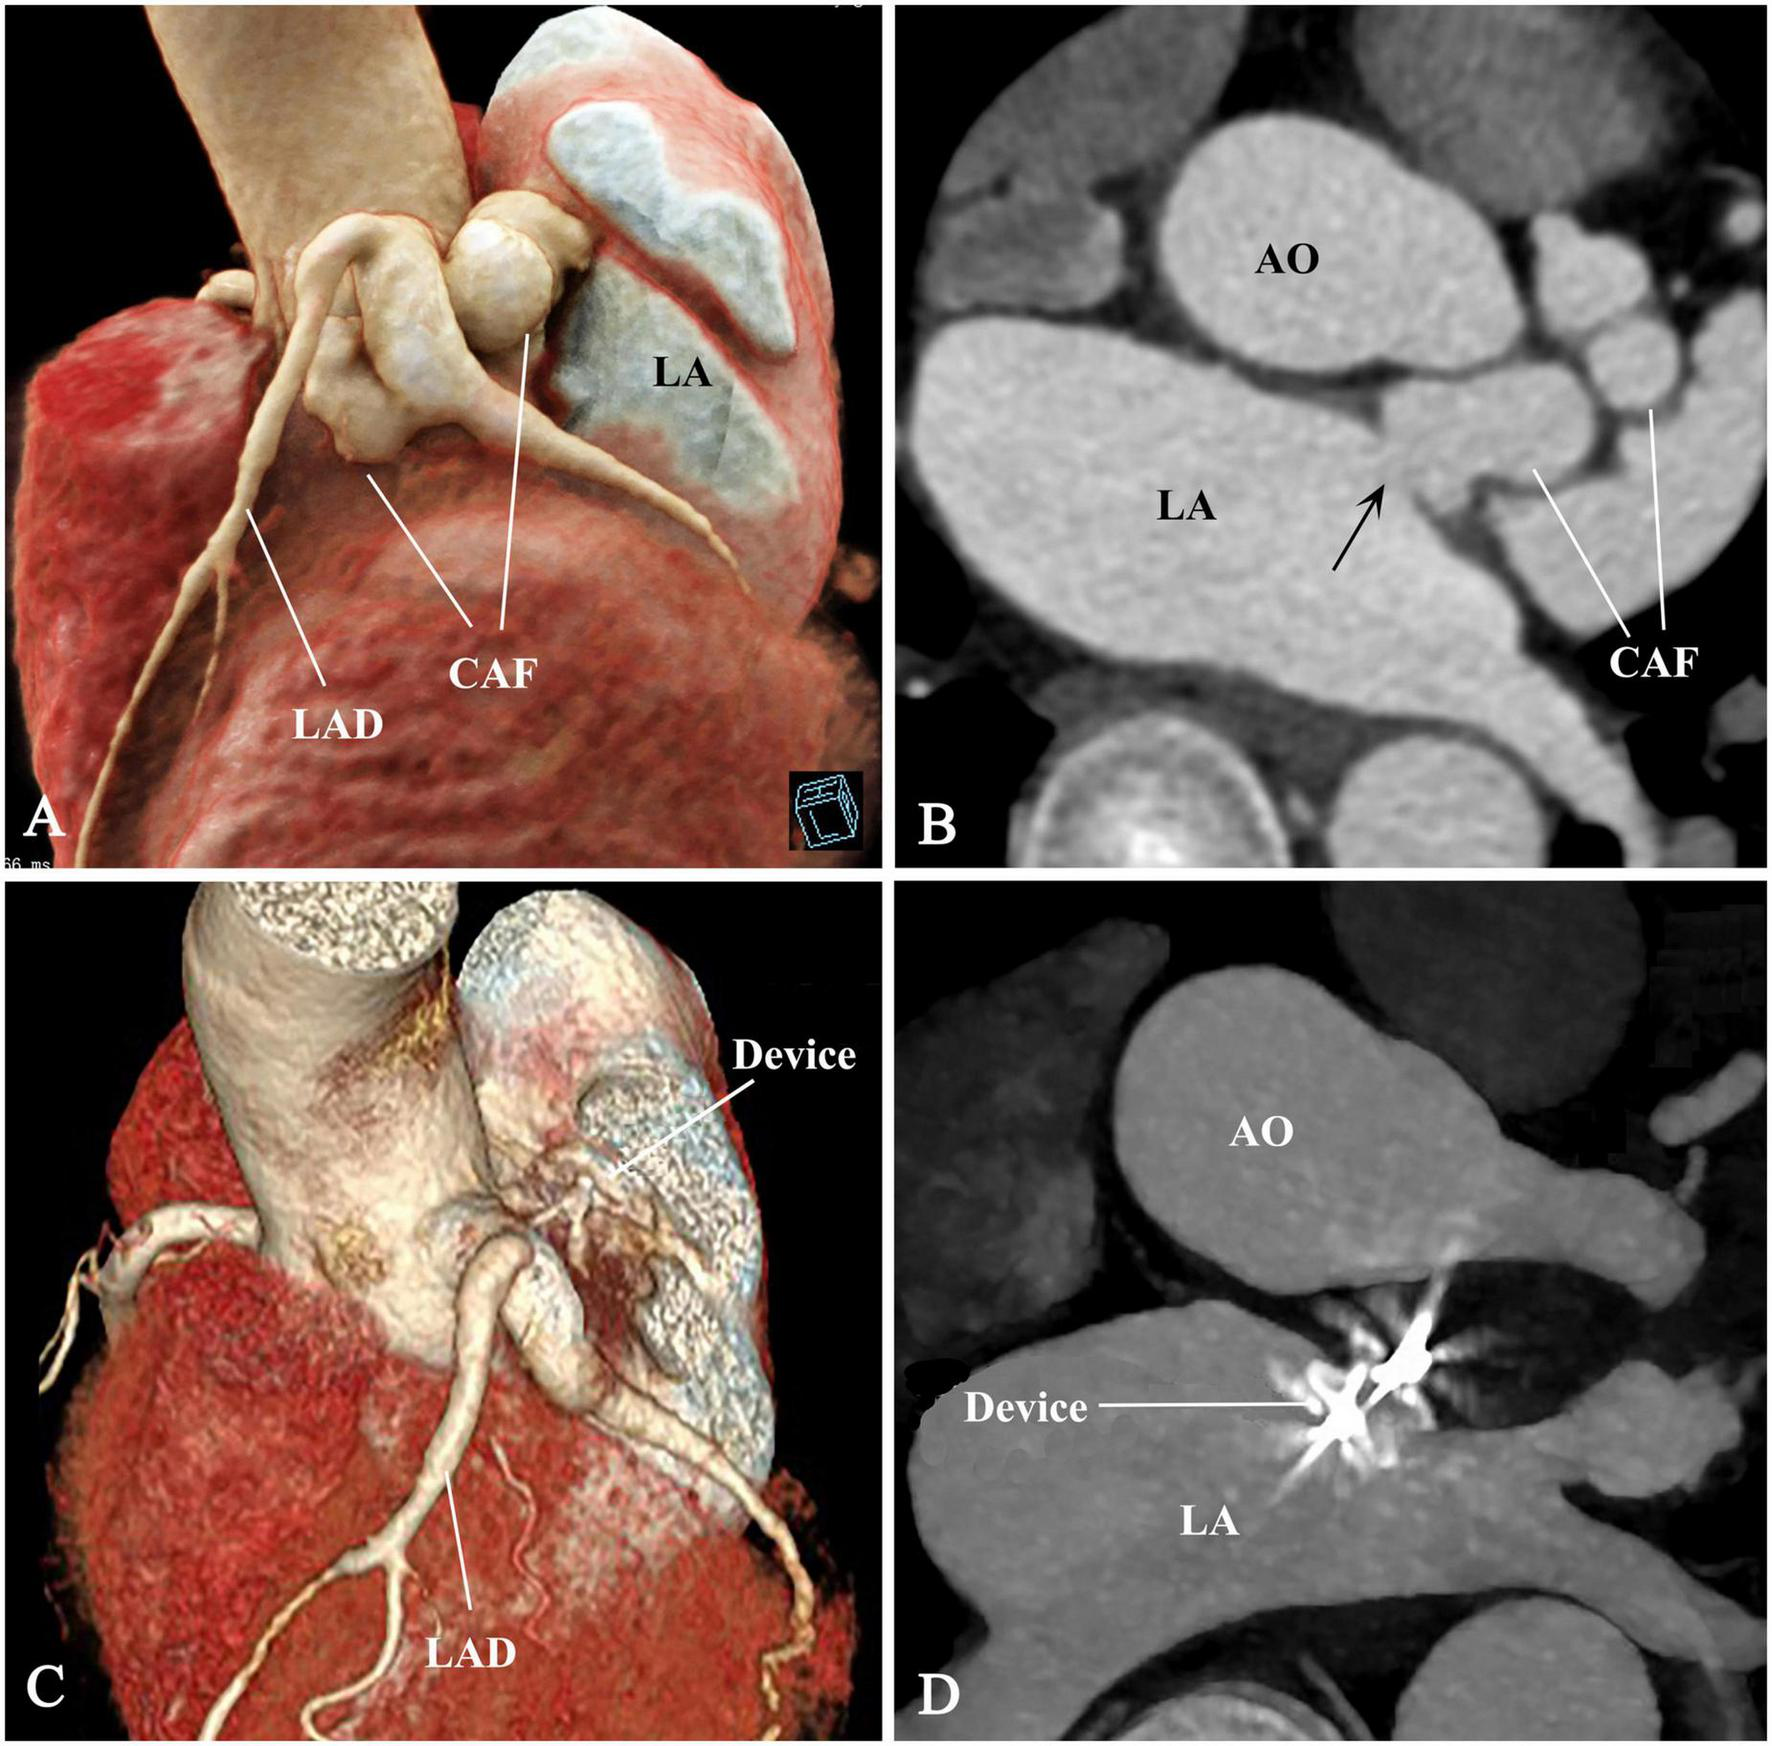

Complete occlusion was achieved immediately after device release. Serial CKMB and troponin levels in the first 48 h were within normal limits. The patient recovered uneventfully and discharged 7 days postoperative. The murmur disappeared post-occlusion. Antiplatelet therapy was maintained on aspirin (100 mg/day) and clopidogrel (75 mg/day) for a year. Medical evaluations including electrocardiograms, TTE, CTA, and stress tests were reviewed during the follow-up period of 18 months. These records demonstrated an appropriate device position and complete occlusion of the CAF and no complications (Figures 3A–D). The Supplementary Figure 1 shows the device and stay-in-suture use.

FIGURE 3

Pre- and post-procedural comparison of CAF. (A–D) The CAF disappeared and thrombogenesis occurred from distal to proximal segment of the CAF. CAF, coronary artery fistula; AO, ascending aorta; LAD, left anterior descending branch; LA, left atrium; arrow, fistulous drainage orifice.